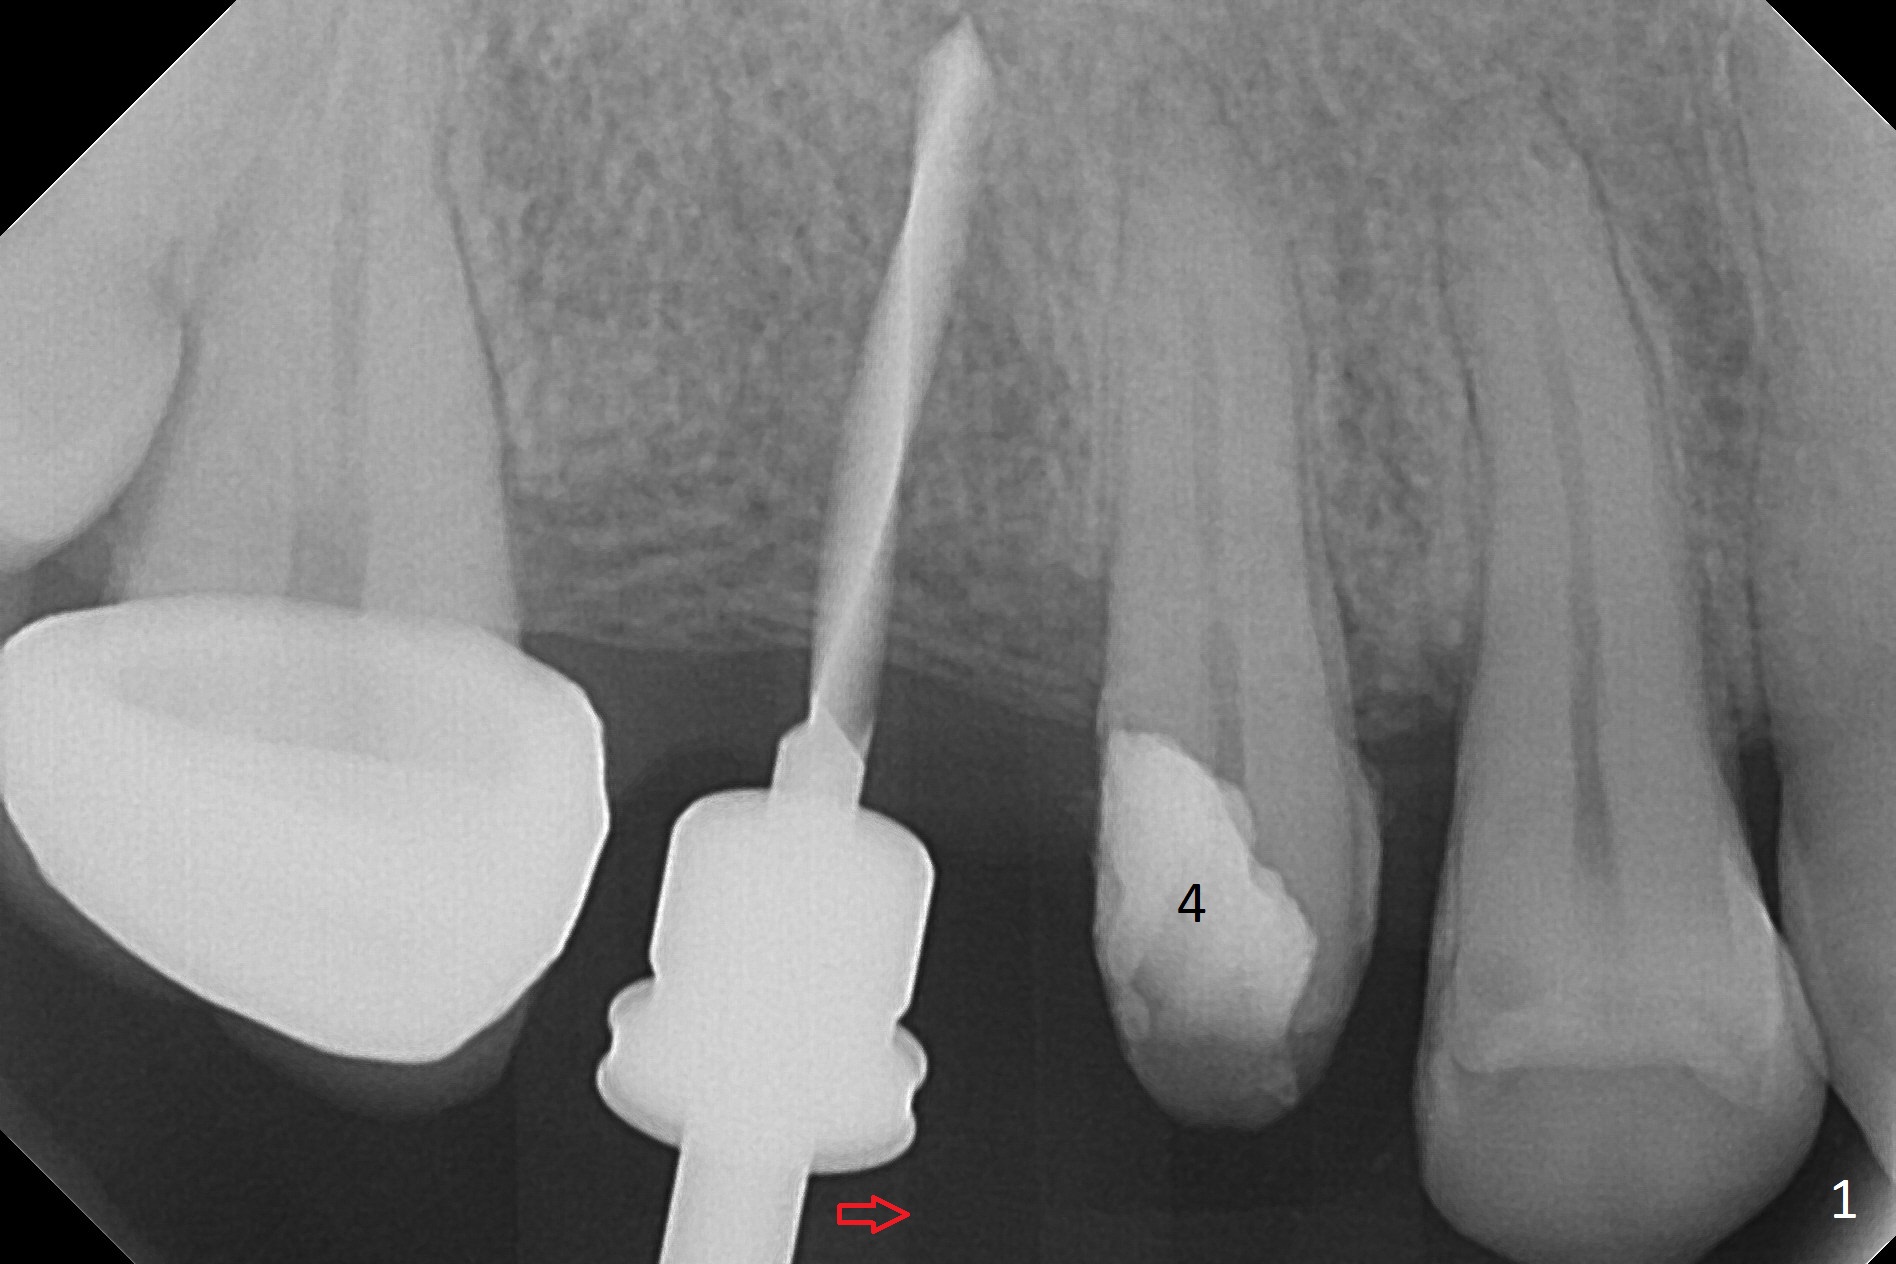

When the bridge is partially removed, the tooth #4 is found to have extensive caries. IRM is placed following carious removal (Fig.1). Magic Split testing shows that the bone density is high (flapless). Osteotomy is initiated by 1.6 mm drill, but the handle of the drill needs to shift mesial (Fig.1 red arrow). When the latter is done, the whole drill (2 mm) needs to move distal (Fig.2 double red arrows). When a 4.5x14 mm drill finishes the osteotomy, it is in the middle of the edentulous space (Fig.3). After use of 5 mm tap, a 5.3x14 mm implant cannot reach the depth (Fig.4,5). Following increase in osteotomy depth from 16 to 18 mm (gingival margin) until 5 mm drill in diameter, the implant placement level is more ideal (Fig.6,7, slightly subcrestal) with insertion torque maintaining at >55 Ncm. The sinus floor (Fig.4 arrowheads) may be penetrated when the osteotomy depth increases (Fig.7 *), but the sinus membrane remains intact.